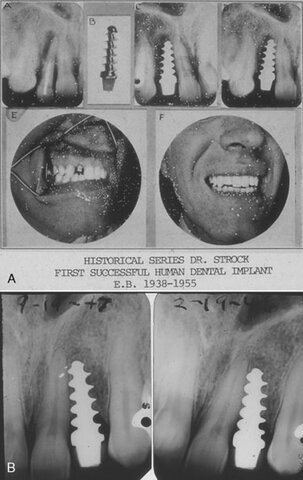

• Primeras prótesis dentales

2900 BCE

Primeras prótesis dentales

Primeros ejemplos conocidos de prótesis dentales, se deben a la artesanía de los etruscos y otras civilizaciones. Fueron fabricados por metalúrgicos; los médicos y cirujanos barberos se encargaban de realizar las exodoncias, mientras que los orfebres y otros artesanos se dedicaban a fabricar el alambre de oro que se usaba para fijar dientes móviles.